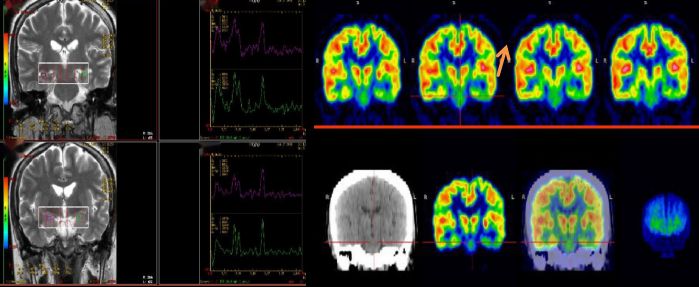

25歲,男,癲癇反復發作  MRS:雙側海馬區NAA降低,提示:神經元缺失;PET顯像提示:左側顳葉代謝減低,手術切除,術后病理提示符合局部腦組織缺氧病理改變,術后患者明顯好轉。